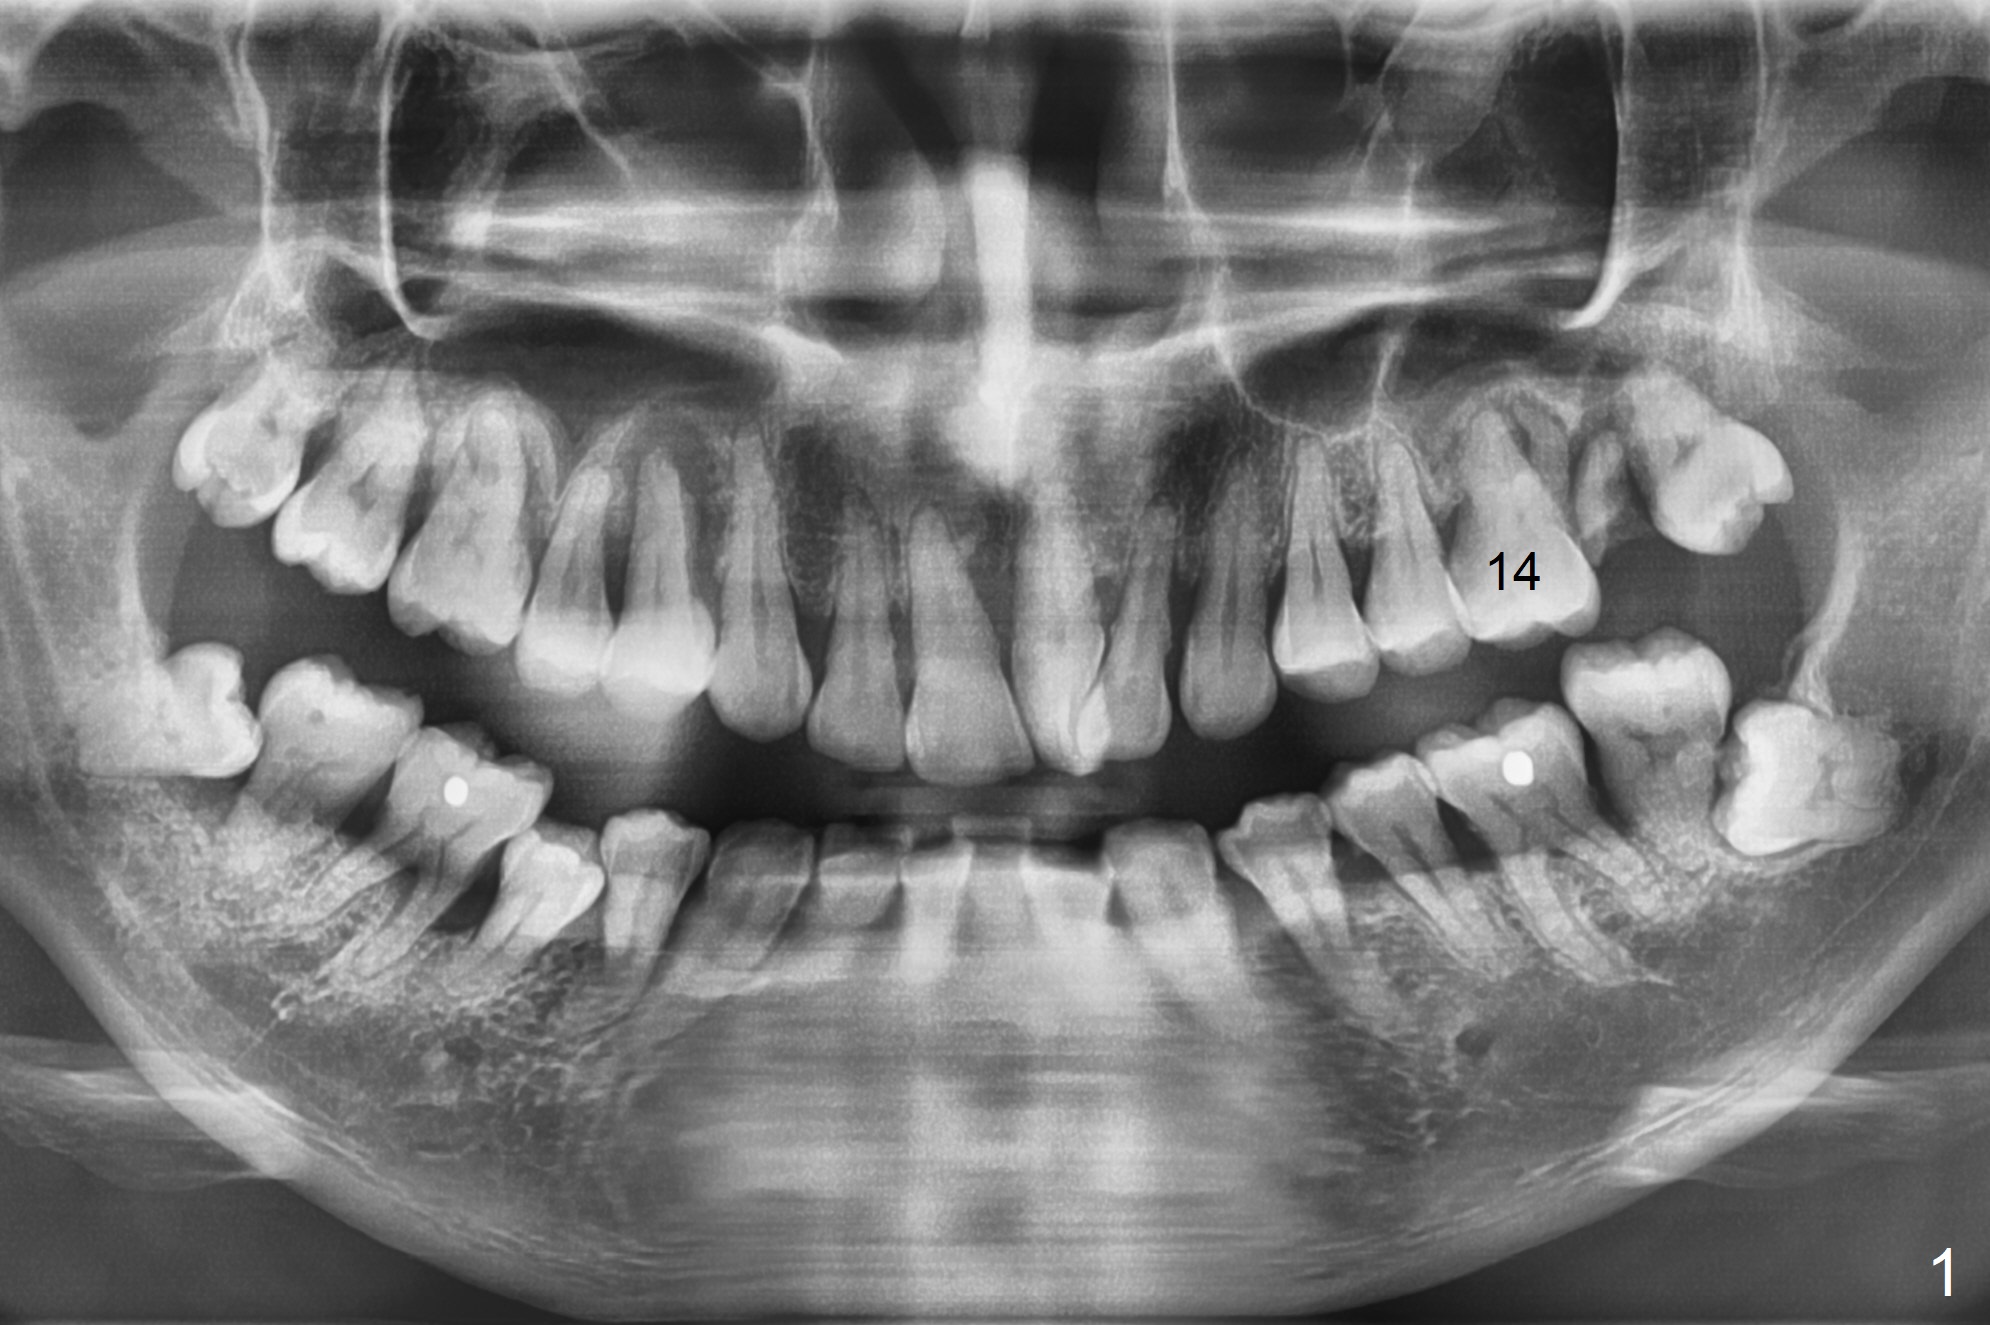

A 34-year-old man (smoker (4 cigarettes per day)) has advanced periodontitis (Fig.1). After upper quadrant SRP, the teeth #14 and 15 are extracted with removal of granulation tissue from #14 palatal socket. Following copious irrigation with NS, a 10x20 mm Osteogen plug is inserted into #14 and 15 sockets. The plug is fixed in place with 4-0 Chromic Gut suture (2 of figure-8 fashion, Fig.2).